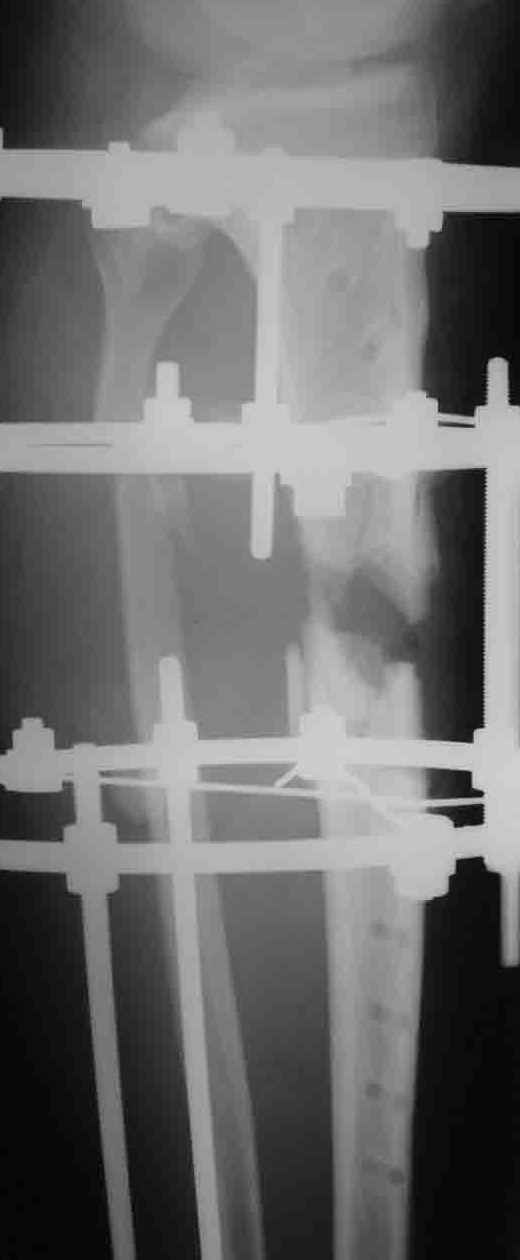

На операции после удаления пластины вывалился промежуточный свободный фрагмент,оставлять его посчитали нецелесообразным. После его удаления вскрыли костномозговой канал, зашили рану и наложили аппарат. После заживления раны концы отломков сблизили. Возможно, всё это же можно было бы сделать одномоментно и на стержне. Но как то мы не решились забить гвоздь при наличии большой раны и костного дефекта. Сейчас 2 недели после операции, больной ходит при помощи костылей с одинаковой нагрузкой на обе ноги. Укорочение в итоге 1,5 см. Обязуюсь показать снимки через пару месяцев.